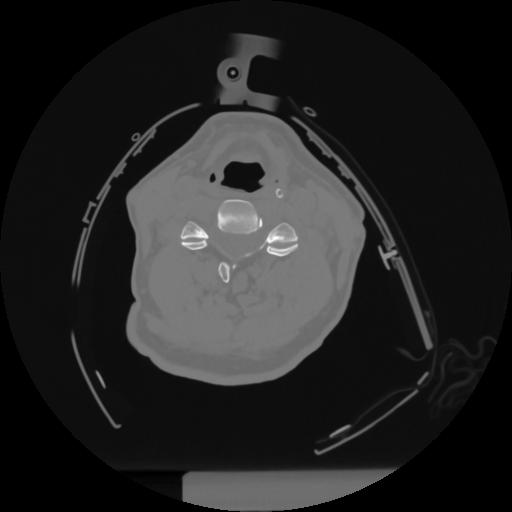

12 P.BLANDAS,,Vol,0.5,P.BLANDAS,,